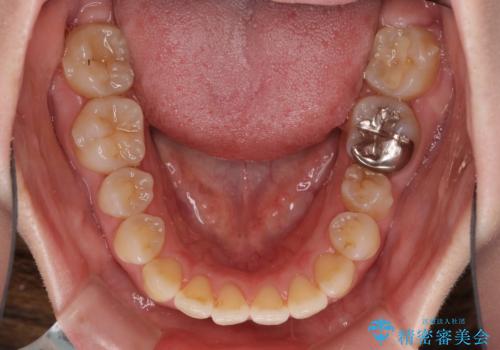

口元の突出感を改善 インビザラインによる非抜歯矯正

- 前歯がデコボコした上に口元が閉じにくいことを気にして来院された患者様です。

IPR(歯と歯の間を削る)と側方拡大では口の閉じにくさは改善できそうになく、一方で抜歯矯正を行うほどの突出感は認められませんでした。

親知らずを全て抜去し、歯列全体を後方に移動させることで口元の閉じにくさいを改善していくこととしました。

インビザラインでの歯列全体の後方移動は時間がかかりますが、しっかりと装着時間を守っていただいたので、スッキリとした口元に仕上げることができました。